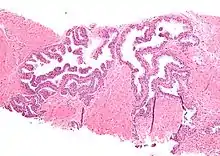

| Micrograph showing high-grade prostatic intraepithelial neoplasia. H&E stain. | |

HGPIN typically has one of four different histologic patterns:[2]

- tufted (fascicular patterning)

- micropapillary,

- cribriform and,

- flat.

Microscopically, PIN is a collection of irregular, atypical epithelial cells. The architecture of the glands and ducts remains normal. The epithelial cells proliferate and crowding results in a pseudo-multilayer appearance. They remain fully contained within a prostate acinus (the berry-shaped termination of a gland, where the secretion is produced) or duct. The latter can be demonstrated with special staining techniques (immunohistochemistry for cytokeratins) to identify the basal cells forming the supporting layer of the acinus. In prostate cancer, the abnormal cells spread beyond the boundaries of the acinus and form clusters without basal cells. In HGPIN, the basal cell layer is disrupted but present. PIN is primarily found in the peripheral zone of the prostate (75-80%), rarely in the transition zone (10-15%) and very rarely in the central zone (5%), a distribution that parallels the zonal distribution for prostate carcinoma.[6]

Several architectural variants of PIN have been described, and many cases have multiple patterns. The main ones are tufting, micropapillary, cribriform, and flat. Although these different appearances may cause confusion with other conditions, they have not been found to be of clinical importance. Rarer types are signet-ring-cell, small-cell-neuroendocrine, mucinous, foamy, inverted, and with squamous differentiation.[3]